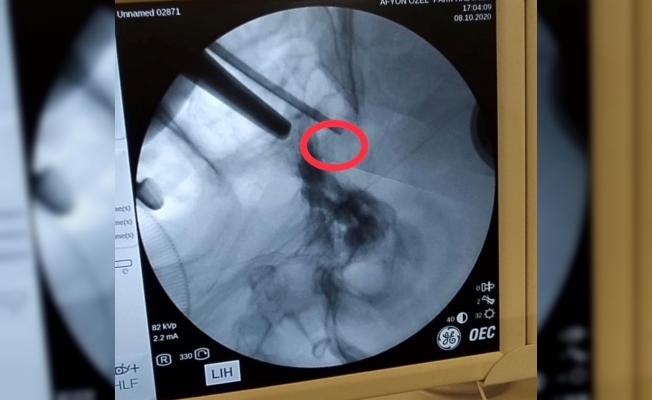

Görme kaybıyla kentteki özel bir hastaneye başvuran ve ismi açıklanmayan Uşaklı 72 yaşındaki hastaya yapılan tahlil ve tetkikler sonucunda hipofiz bezine yerleşmiş ve kafa tabanındaki sinirlere bası yapan bir tümörün varlığı tespit edildi. Beyin ve Sinir Cerrahi Uzmanı Op. Dr. Celal Özbek Çakır tarafından operasyon yapılmasına karar verildi. Ameliyata alınan hastanın burun deliklerinden girilerek beynindeki tümör alındı.

Operasyon sonrası açıklamalarda bulunan Çakır, transsfenoidal cerrahinin burun boşluğundan girilip hipofiz tabanına ve oradan hipofize ulaşılıp yapılan cerrahi olduğunu söyledi. Çakır, "Hastamız da 72 yaşında, ani gelişen göz kapağında düşme, görme kaybı ve şiddetli baş ağrısı ile bize geldi. Hastanın tetkiklerinde sella dediğimiz kafa tabanında hipofiz bezinin yerleştiği boşlukta büyük bir kitle ve buna bağlı bu bölgedeki kranial sinirlerin bası altında kaldığını görerek cerrahi kararı aldık. Hastaya transsfenoidal girişimle tümörü tamamen boşalttık ve problemsiz olarak servise aldık" dedi.